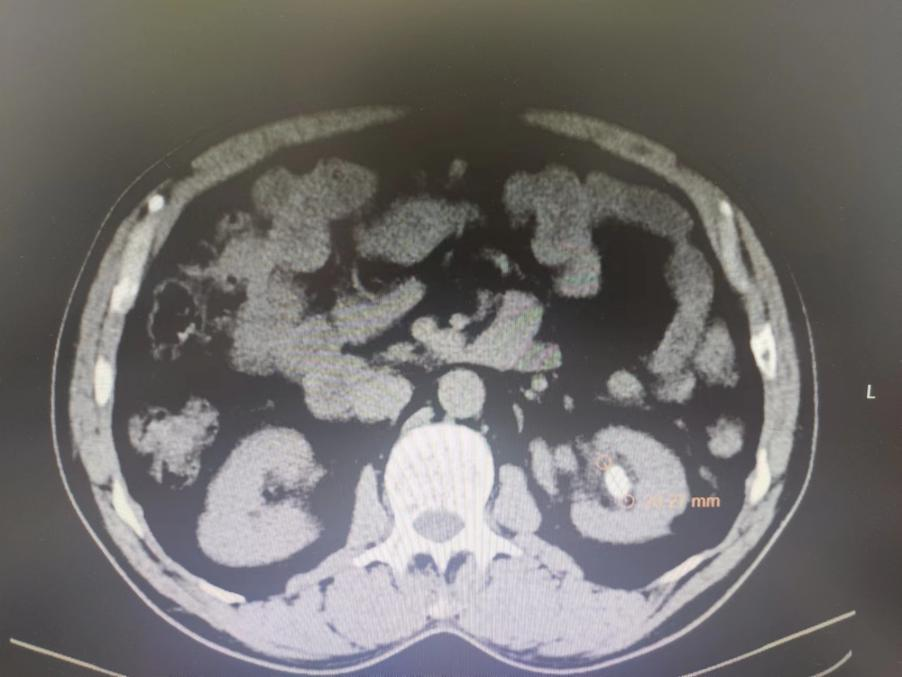

近日,舟曲县人民医院综合外科医师团队,在天津帮扶专家杜君副院长、陈业刚主任及张华主任的带领、指导下完成全县首例“经皮肾镜激光碎石取石术”。

经皮肾镜激光碎石取石术是一种新型微创手术,可通过皮肤上的小刺伤(最长约1cm)在腰部建立一条从皮肤到肾脏的通道,通过通道把肾镜插入肾脏,利用激光、超声等碎石工具,把肾结石击碎并取出。经皮肾镜碎石术的优势具有损伤小、痛苦轻、取石彻底、恢复快等优点,适应症较广。

患者结石体积大,位置高,体外碎石效果不理想,且患者既往曾多次行体外冲击波碎石治疗,均未能完全解决问题,经该院医师及天津帮扶专家综合讨论患者病情后,决定行经皮肾镜激光碎石取石术。5月11日上午,在全麻下完成了经皮肾镜激光碎石取石术,手术过程顺利,患者术后恢复良好,手术取得了良好的治疗效果。